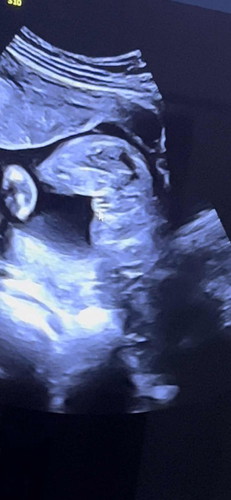

แบบนี้แม่ๆคิดว่าเป็นหญิงหรือชายคะ

ตอนแรกไปซาวครั้งก่อนหมอบอกเป็นชาย ครั้งนี้เป็นแบบนี้หมอบอกได้หญิง คิดว่าไปในทางไหนคะ

ตอนแรกของบ้านนี้ก็เห็นแบบนี้ค่ะ เราก็คิดว่าผู้หญิงมันไม่มีอะไรโด่แถมเป็นกลีบๆแบบนี้เลย แต่หมอบอกว่ามันยังไม่ชัดเจน รอไปก่อน ซาวไปซาวมา โด่มาเฉย งงในงง มายังไง น่าจะรออีกรอบเพื่อให้แน่ใจดีกว่าแม่ บ้านนี้หมอบอกมันชัดเจนแล้วสรุปชายให้ในใบเรียบร้อยไม่ได้รอได้ลุ้นเลย🤣

เหมือนเราเลยแม่ตอน16w3dบอกเห็นจู๋ พอ19w5dบอกได้ลูกสาว😂

รอคอนเฟิร์มอีกรอบก็ได้ค่ะแม่ แต่น่าจะได้หญิง

ผญค่ะ ไม่มีแหลมๆยื่นออกมา

หญิงค่ะ เป็นกลีบเลย